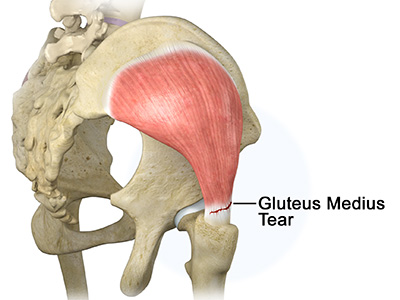

- Gluteals: These are the muscles that form the buttocks. There are three muscles (gluteus minimus, gluteus maximus, and gluteus medius) that attach to the back of the pelvis and insert into the greater trochanter of the femur.

Hip Dislocation Gluteus Tendon Tear

Gluteus Tendon Tear Hip Abductor Tears

Hamstring Injuries Gluteus Medius Tear

Gluteus Medius Tear Hip Pain